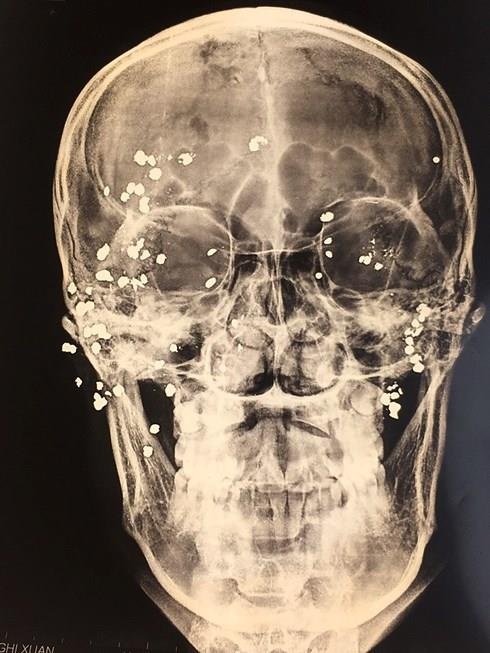

Các bác sĩ cho bệnh nhân chụp X-quang và CT sọ não. Kết quả cho thấy có rất nhiều dị vật cản quang ở hàm mặt và hốc mắt 2 bên của bệnh nhân.

| Hình ảnh chụp Xquang. Ảnh: Infonet. |

Trong 2 giờ, các bác sĩ đã tiến hành mổ đi qua các vết sẹo, lấy được dị vật là mảnh đạn hoa cải có đường kính khoảng 1-2 mm, đạn dạng bi. Sau khi bắn vào cơ thể, dị vật dẹt, mỏng dính, hòa vào tổ chức, không sờ thấy bằng tay nên rất khó định vị để tìm và lấy dị vật ra. Sau đó, các bác sĩ tiếp tục thăm dò vết thương và lấy được 39 viên đạn, trên tổng số 50 viên đạn bị bắn.

Số viên còn lại nằm sâu trong ổ mắt và thần kinh mạch máu quan trọng nên không thể tiếp cận lấy ra được hoặc lấy ra sẽ làm ảnh hưởng chức năng. Các bác sĩ đã phải cắt lọc tổ chức hoại tử, làm sạch và khâu lại vết thương.